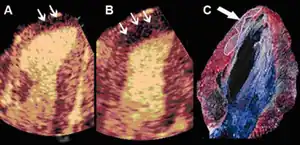

Infarct size determination

Representative example of real-time myocardial contrast echocardiography images showing lack of perfusion that corresponds to infarcted area before (A) and during adenosine infusion (small arrows) (B). Note that adenosine increases the infarct size determination. Necrotic area was determined as the region that failed to demonstrate brick red staining, appearing pale yellow, by triphenyl-tetrazolium chloride staining (arrow) (C).

Adenosine infusion, can increase perfusional defect, as a result per an animal study indicates that "a better correlation between the echocardiographic measurements and the necrotic area determined by tissue staining". [39]